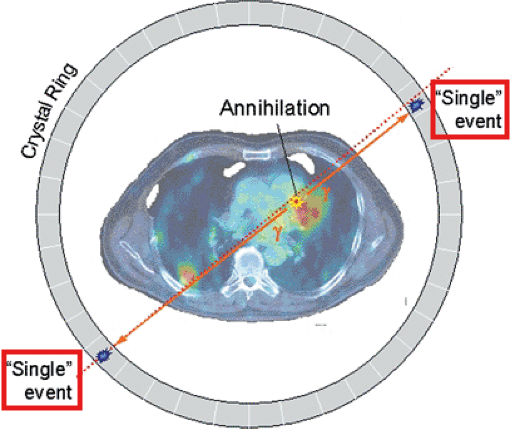

Picks up 2 photons – the photons emitted from an annihilation reaction

What is the relationship between each detector pair inside the ring of detectors in a PET camera?

Each detector works together with the detector opposite to it – allows it to pick up on a line of response

What is a line of response?

When the photons from an annihilation reaction are emitted, they will travel in opposite directions of one another – makes a 180-degree line almost

How does a ‘dot’ from our image translate from the reaction at the PET detectors?

The detectors create a dot on our scanned image from the point at which the 2 photons are overlapping – or where they cross each other in the ring of detectors but we still need more information to specifically determine it!

What is needed in order for the PET detectors to determine where an annihilation reaction occurred on a line of response?

Requires multiple line of responses to figure out where the intersection of where the annihilation reaction took place

Is a line of response able to determine where the photon originated from?

No, it’s only able to determine where the annihilation took place

Cannot tell us where the positron was ejected from as it will travel away from the original nucleus